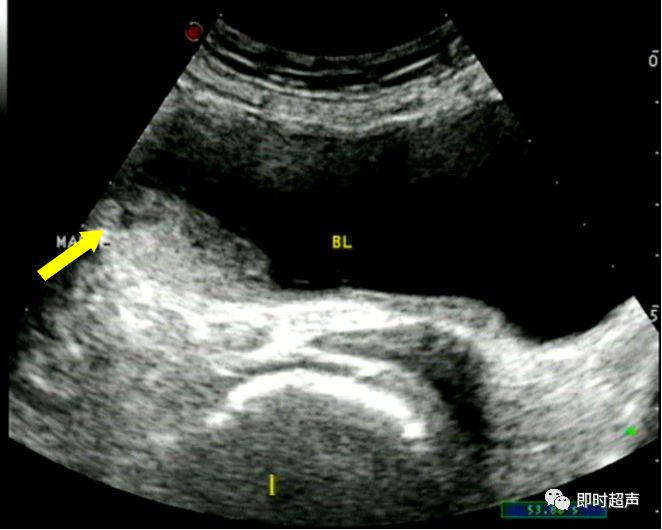

患者,男性,40岁,有排尿刺激性症状 ,并有尿潴留。临床实验室检查:尿常规: (-),超声声像图如下:

右肾 左肾

经腹壁扫查 经直肠扫查

膀胱内可见导尿管气囊回声(箭头),膀胱右后方可见大小约9.2cm×6.5cm×8.3cm囊状物(虚线),膀胱右侧壁与囊状物相通,窦道(白箭头)宽约0.6cm。

诊断思路:

- 该患者为中年男性,有排尿刺激症状

- 超声图像显示膀胱右侧方可见一囊状物与其相通,并见窦道。挤压后囊状物变小

- 综上所述,诊断应考虑巨大膀胱憩室